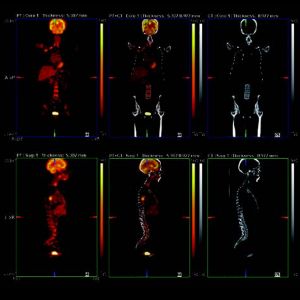

IMAGE FUSION

MiE’s Image Fusion for scintigraphy and x-ray images enhances the diagnostic possibilities. The program evaluates the different structures, resolution, acquisition geometries and regions. Rotation, translation (shift) and scaling will be adjusted.

The process operates multi modal and automatic. The fusion allows the combined usage of the morphologic information of the x-ray and the functional information of the scintigraphy in one image.